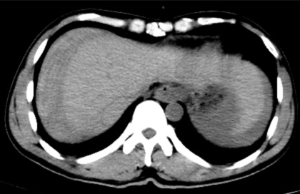

據悉,患者既往有多年乙型肝炎病史,突發右上腹劇烈疼痛入院。患者入院時血壓70/40mmHg,心率110次/分,全腹壓痛。血常規血紅蛋白87g/L,甲胎蛋白>1210 ng/ml。腹部B超檢查及CT平掃檢查示“肝腫瘤并出血,腹腔積血積液”。